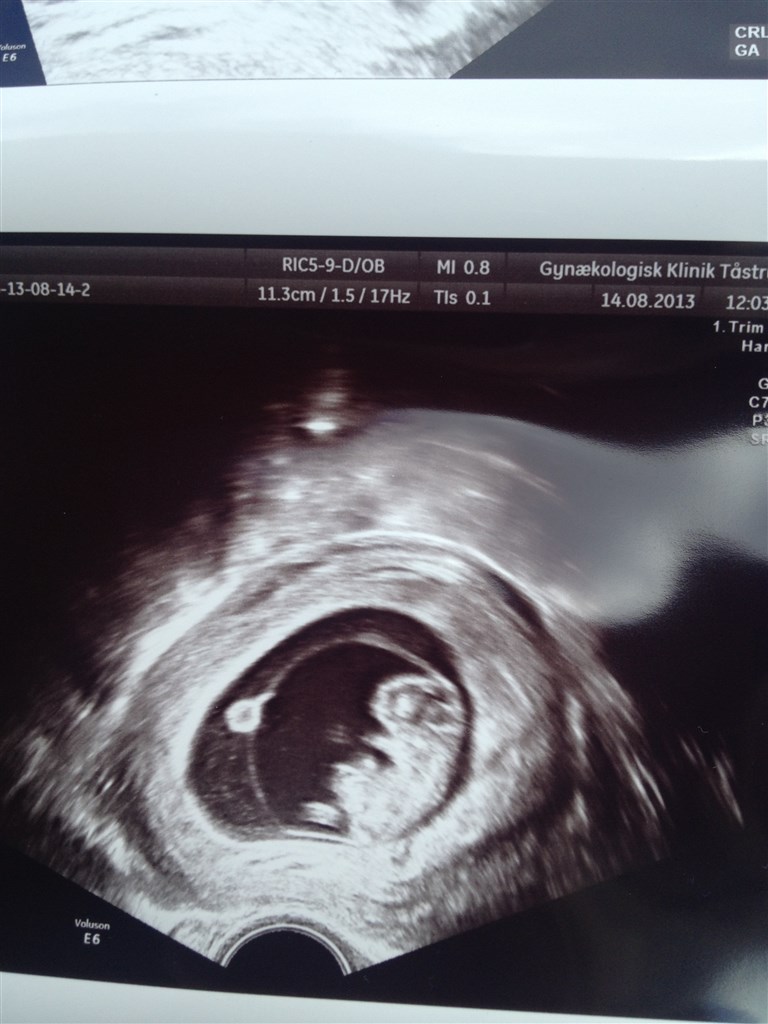

Endelig, efter gynækologen har holdt ferie har jeg ventet 4 uger på at komme til scanning. Sidste gang gik jeg med beskeden om at de kun kunne se hjerteblink og faktisk ikke kunne se nogen baby udenom og havde en blødning som lå meget skidt i forhold til graviditeten.

Men nu gik jeg med beskeden 10+0 med den fantastiske lille baby og alt ser bare helt perfekt ud!

terminen rykket 2 dage frem til 12. Marts.